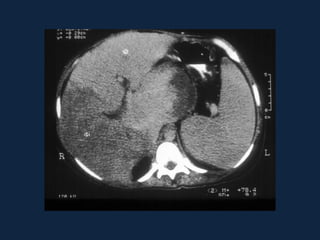

ESQUISTOSSOMOSE MANSÔNICA

• Intensa reação

inflamatória que

resulta em fibrose

periportal.

• Atrofia do lobo direito,

hipertrofia do lobo

esquerdo e

hipertensão portal.

Distribuição perivascular

• Esquistossomose

– Fibrose periportal

– Hipertensão pré-sinusoidal

– US: Aumento da ecogenicidade

periportal (“céu estrelado”)

– TC:

• SC: Bandas hipodensas

periportais

• CC: contrastação tardia

– RNM:

• T1: Bandas fibrosas 

• T2: Bandas fibrosas 

• Contraste tardio